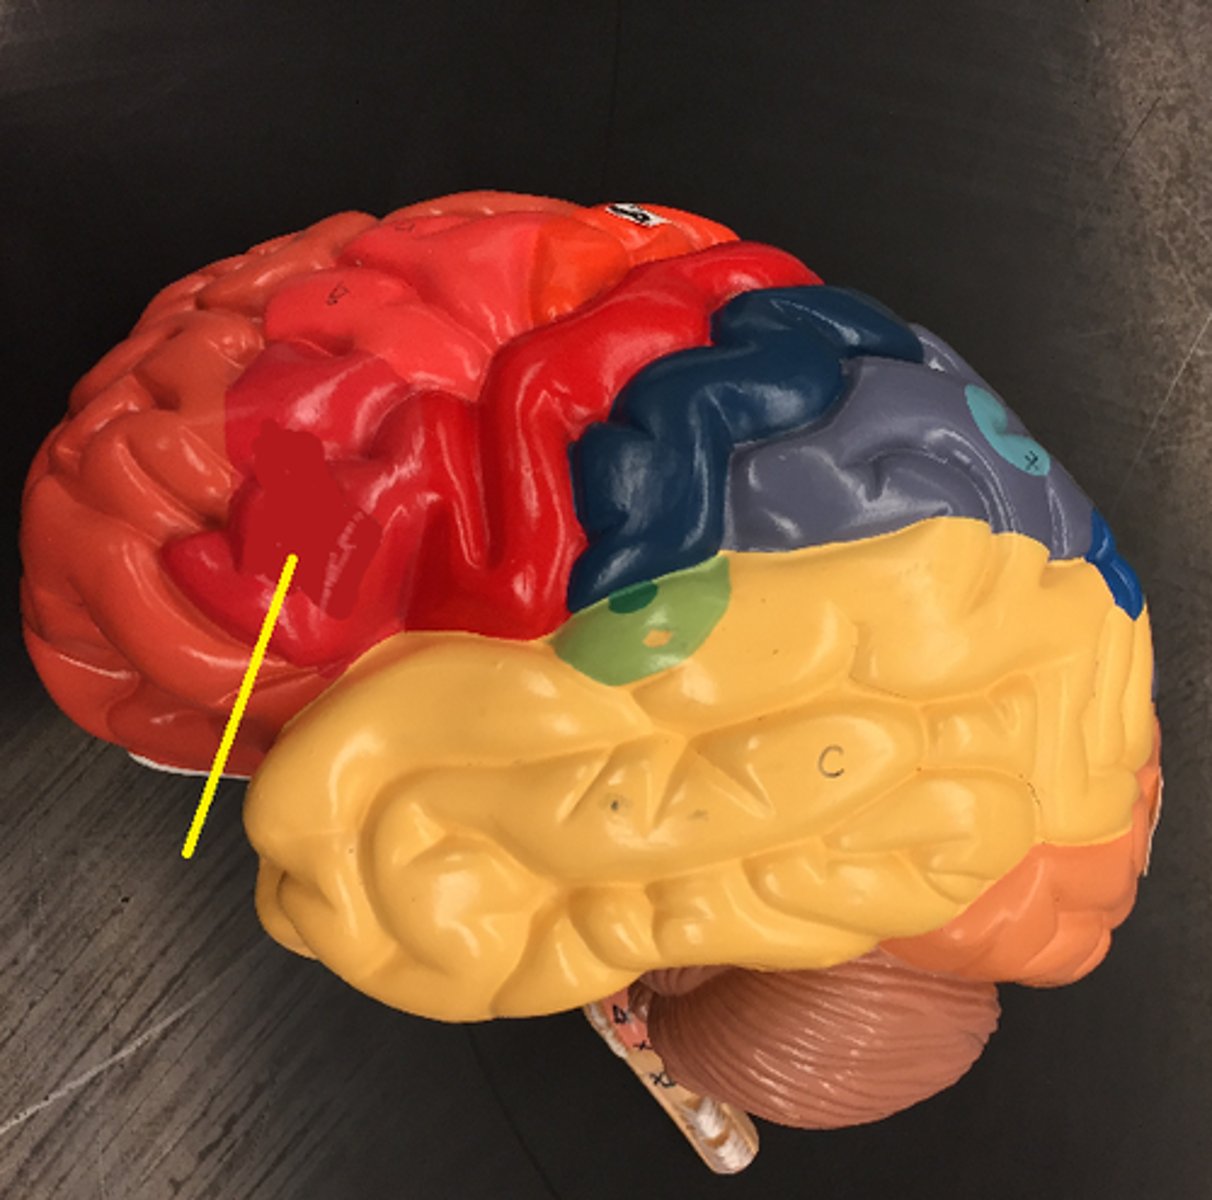

central sulcus

lateral sulcus

frontal lobe

temporal lobe

parietal lobe

occipital lobe

Broca's area

Prefrontal cortex

Premotor cortex

Wernicke's area

Primary visual cortex

Primary auditory cortex